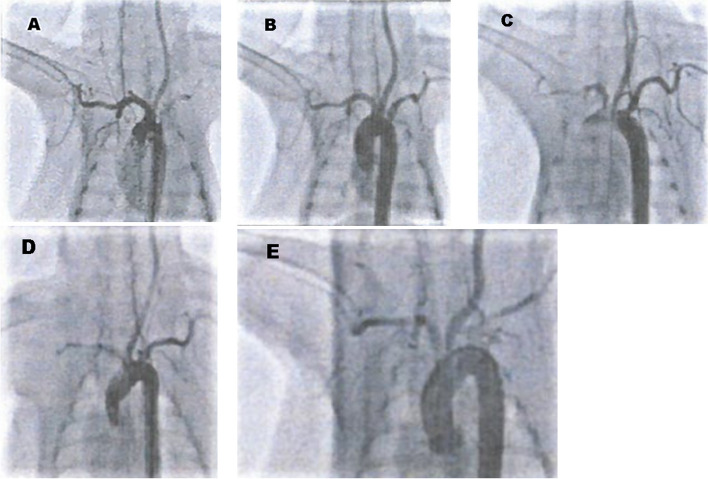

Methods: Aneurysms were induced in 20 New Zealand white rabbits which were randomized to three follow-up groups according to the time elapsed after EMBOPIPE implantation (28, 90, and 180 days). Additional EMBOPIPEs were implanted in the abdominal aorta to cover the renal artery in nine rabbits. Angiography was performed immediately after device placement in all groups. Aneurysm occlusion, patency of renal arteries, and pathological outcomes were assessed. For the in vitro experiments, we measured the thrombogenic potential of EMBOPIPEs (n = 5) compared with bare stents (n = 5) using the Chandler loop model. Evaluation indicators were the platelet counts, macroscopic observations and scanning electron microscopy.

Results: EMBOPIPEs were successfully deployed in 19 of 20 rabbit aneurysms (95.0%). The rates of complete or near-complete aneurysm occlusion were 73.3%, 83.3%, and 100% in the 28-, 90-, and 180-day groups, respectively. All renal arteries covered by EMBOPIPEs remained patent, and the mean difference in renal artery diameter before and after the device placement in the three groups was 0.07 mm, 0.10 mm, and 0.10 mm, respectively (p = 0.77). Renal pathology was normal in all cases. The pathological findings of the aneurysms were as follows: thickened and adequate neointimal coverage at the aneurysm neck, minimal inflammatory response, near-complete smooth muscle cell layer, and endothelialization along the device. In vitro experiments showed that the platelet counts were significantly higher in EMBOPIPE blood samples than in bare stent samples and that platelet adhesion to the device was lower in the EMBOPIPE stent struts compared with bare stent struts through macroscopic observations and scanning electron microscopy.